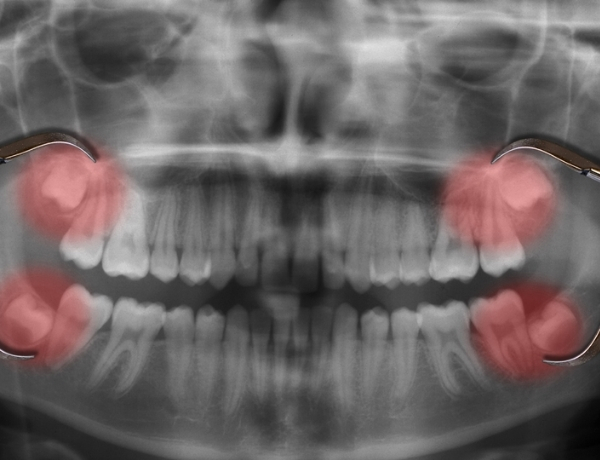

Özellikle enfekte olmuş, çürümüş ya da çevre dokulara zarar veren dişlerin çekilmesi, daha ciddi sorunların önüne geçilmesine yardımcı olur.

Diş çekimi; ağrı, iltihap ve kötü koku gibi problemleri ortadan kaldırarak ağızda rahatlama sağlar. Ayrıca diş dizilimini bozarak çene yapısında baskı oluşturan veya diğer dişlerin sağlığını tehdit eden dişlerin alınması, genel ağız dengesini korur.

Diş eti hastalıklarının ilerlemesini önler ve protez, implant gibi ileri tedavilere zemin hazırlar.